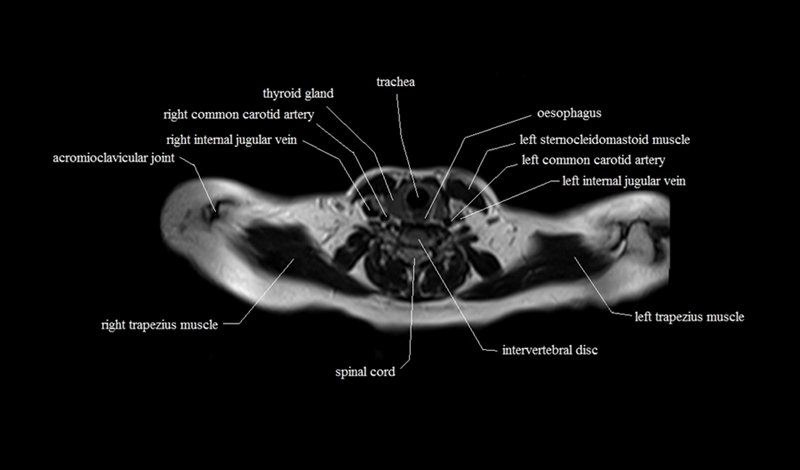

MRI Axial Cross Sectional Anatomy of Chest

This MRI chest (thorax) axial cross sectional anatomy tool is absolutely free to use. Use the mouse scroll wheel to move the images up and down, or alternatively, use the tiny arrows (→) on both sides of the image to navigate through the images. For a more detailed view, double-click the image to view it in full screen, and use the menu in the top right-hand corner to view individual slides or play them in a loop.